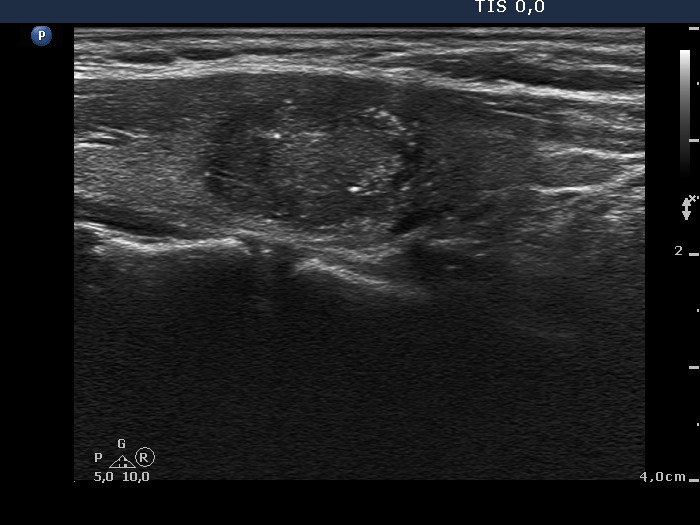

Papillary carcinoma (histological diagnosis) |

This case is less edifying or may be more edifying. Compared with the previous case, the granules here are less bright. Nevertheless, great proportion of them belong to punctate echogenic foci (arrows). It is worth to compare these with non-specific granules (arrowheads). |